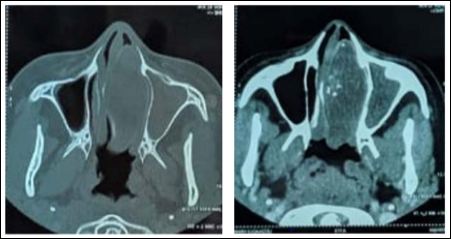

The facial CT scan showed a voluminous and heterogeneous polypoid leftnasal process with calcifications, measuring approximately 58mm x 25.4mm, expanded on 36mm, arriving posteriorly to the ipsilateral choana, invading the right ethmoidal labyrinth with partial bone erosion, till the nasal septum which is repressed with partial lysis of its bony portion; laterally, the process attains the medial wall of the right maxillary sinus, causing sinus retention (Figure 1).

Figure 1: (A) CXR showed elevated left hemidiaphragm with bowel loop suspecting diaphragmatic hernia. (B) CT axial image confirming part of bowel herniated into the left thoracic cavity.

The facial CT scan is the ideal imaging technique, offering a perfect visualization of the concha bullosa and a clear detection of its mucocele. But, it can’t differentiate between a mucocele and a pyocele. They both appear as a soft-tissue mass with a bony contour, usually causing deviation or compression of surrounding structures. The bony rim is considered the main finding on CT that enables identification of the mucocele into the middle turbinate; if absent, the diagnosis may be confused with a tumour, then an incisional biopsy can be done [2,3]. The absence or inconsistent presence of bony shell could be explained by an underlying mechanism of bone remodelling [2]. Also, a mucopyocele can be suggested in the presence of peripheral enhancement of a mucocele, as shown in our case [3].